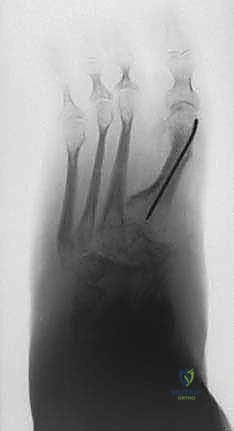

TECHNIQUES EPIPHYSIODESIS OF THE FEMORAL PHYSIS DISTALLY OR THE TIBIAL PHYSIS PROXIMALLYPreparation of the Physis 1. A metal marker is placed over the skin and under the image intensifier, and the level of the physis is identified at its peripheral area (either medially or laterally) (TECH FIG 1A).

2. A 3-mm skin incision is made with a scalpel at the level of the physeal plate on the peripheral side (medially or laterally) (

TECH FIG 1B

).

3. Under image intensification control, a 3-mm-wide osteotome is directed through the skin incision to make a longitudinal split in the periosteum–cortex, and the physeal plate is then penetrated to a depth of about 0.5 cm (

TECH FIG 1C,D

4. The osteotome is rotated to create a hole in the physis and is then withdrawn.

A

--- B C DTECH FIG 1 • A. Patient’s leg under an image intensifier with a metal pointer identifying the level of the femoral physis distally. B. The incision is only 3 mm. C. A 3-mm-wide osteotome is being directed through the skin incision to make a longitudinal split in the periosteum–cortex and the physeal plate. D. A radiographic view of the osteotome penetrating the physeal plate to a depth of about 0.5 cm.Physeal Plate Ablation 1. A 3-mm oval curette is advanced through the skin into the hole of the physis (